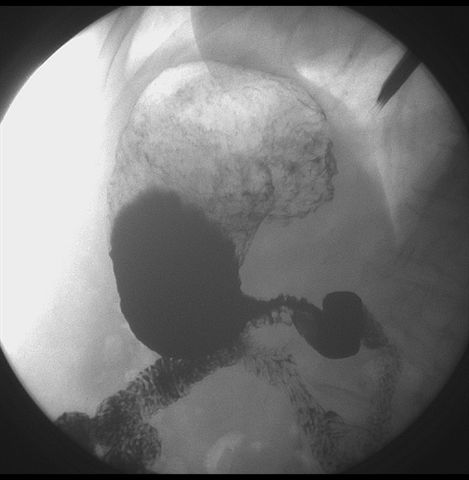

标题: X6872:F,69y,胃部不适。

胃窦至幽门段胃壁僵硬,扩张受限,局部纠集粘破坏,呈杵状。提示溃疡癌变可能性大。

胃窦癌可能性大,建议胃镜活检。钡剂太稀,吃的有点多。

支持考虑胃窦癌可能,胃内滞留液太多,胃窦部僵硬。

胃窦部见钡池影,局部粘膜紊乱,纠集呈杵状改变,胃壁扩张受限,胃窦癌可能性大,建议胃镜检查.

胃窦部管腔扩张度较差,形态略有改变,胃窦粘膜显示欠佳,胃窦部占位可能性大,结合胃镜活检。

胃窦部狭窄、稍僵硬,考虑胃窦癌?建议胃镜检查。

北京肿瘤医院胃镜诊断皮革胃。